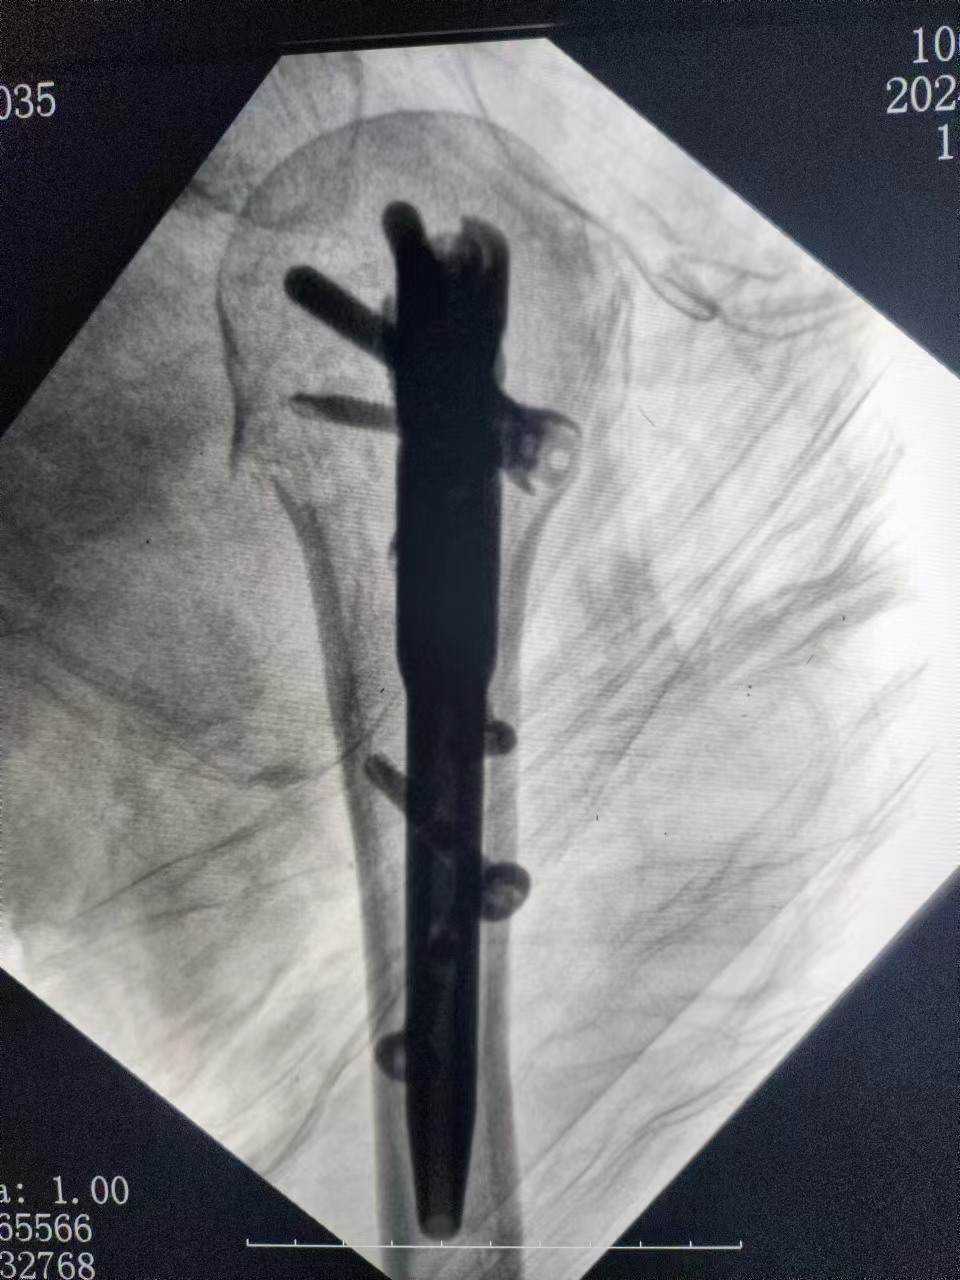

病例一:患者,女,70岁,车祸致左肱骨近端粉碎骨折,在孙院长组织术前讨论后决定行”左肱骨近端粉碎性骨折闭合复位髓内钉内固定术”考虑患者年龄大、基础病较多,微创治疗恢复快,骨三科医疗团队为其行手术治疗,术后功能恢复良好,患者及家属十分满意。 ▲术前 ▲术后 病例二:患者,男,51岁,因滑倒摔伤致左胫腓骨骨折伴后踝骨折,术前准备钢板内固定、髓内钉闭合内固定两种手术方案,通过术前讨论和局部皮肤条件的观察,选用髓内钉闭合复位内固定,骨三科医疗团队主刀下运用多枚克氏针(阻挡+固定+合拢),解决后踝和螺旋劈裂骨折块问题,手术顺利结束。 ▲术前 ▲术后 ▲术后 ▲术后微创小切口 目前,我院骨三科医疗团队已成功完成数例髓内钉手术,临床疗效非常满意。近年来周口人合医院骨三科大力发展微创技术,积极开展各类微创手术,力求打造微创以及快速康复的治疗新标杆,更好地为人民健康保驾护航。 ▲创伤与手足显微外科专家查房查看患者病情 ▲创伤与手足显微外科专家共同探讨患者病情